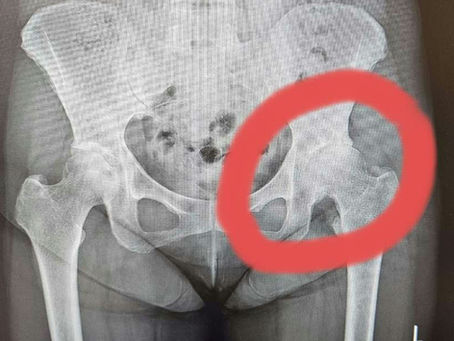

入院二十八日目

本日、入院二十八日目。 考え深いものがありますねぇ。 去年の暮れ 手術を決意した時の私の股関節は 大腿骨と股関節の隙間が 無くなってました。 痛くて歩けない〰️〰️〰️❗😭 そこで手術を5月に決定! 8年も良く耐えてくれました😢 入院初日の5月4日は 病室全室個室で...

5月4日に入院して 5月6日に変形性股関節症の 手術をして頂きました。 今は一日に二度のリハビリの毎日。 本当に先生方や看護師さんには 感謝でございます。m(__)m 思い起こせば。 八年ほど前から 「左の股関節が痛いなぁ~。」 歩きにくくなって来ました。...